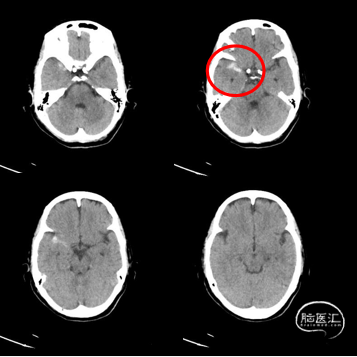

少量出血(SAH?实质?),无神经功能受损。

D0 2022-2-21